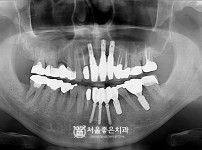

뼈이식 임플란트 2개 - 오스템 임플란트 / 타치과 임플란트 파절상태, 발플 후 임플란트

해당 게시물은 의료법 제56조에 의거하여 로그인 후 열람이 가능합니다.

구분 임플란트